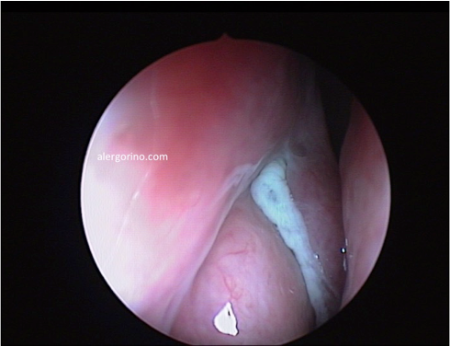

endoscopia nasalendoscopia nasal

El diagnóstico se realiza mediante la historia clínica y una endoscopia nasal que proporcionan datos como la presencia de pólipos, la descarga mucopurulenta y el edema o la obstrucción de las áreas de drenaje de los senos paranasales. Si no se produjera una respuesta al tratamiento médico se evalua la situación de los senos paranasales mediante una tomografía computarizada (TC).

Los objetivos del tratamiento son: controlar la infección, reducir el edema del tejido, facilitar el drenaje, mantener la aireación de los senos paranasales, rompiendo el ciclo vicioso que conduce a la cronicidad. El tratamiento de la SC, con y sin póliposis, suele puede ser "en bocadillo": médico – quirúrgico – médico. Principalmente los lavados nasales en forma de duchas nasales, corticoides intranasales, antibióticos en caso de sobre-infección. La cirugía endoscópica está indicada cuando fracasa el tratamiento médico. En caso de la SC fúngica es imprescindible la apertura y limpieza adecuadas de los senos afectados.